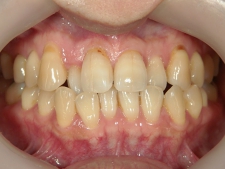

矯正歯科 治療前 正面

矯正歯科 治療後 正面